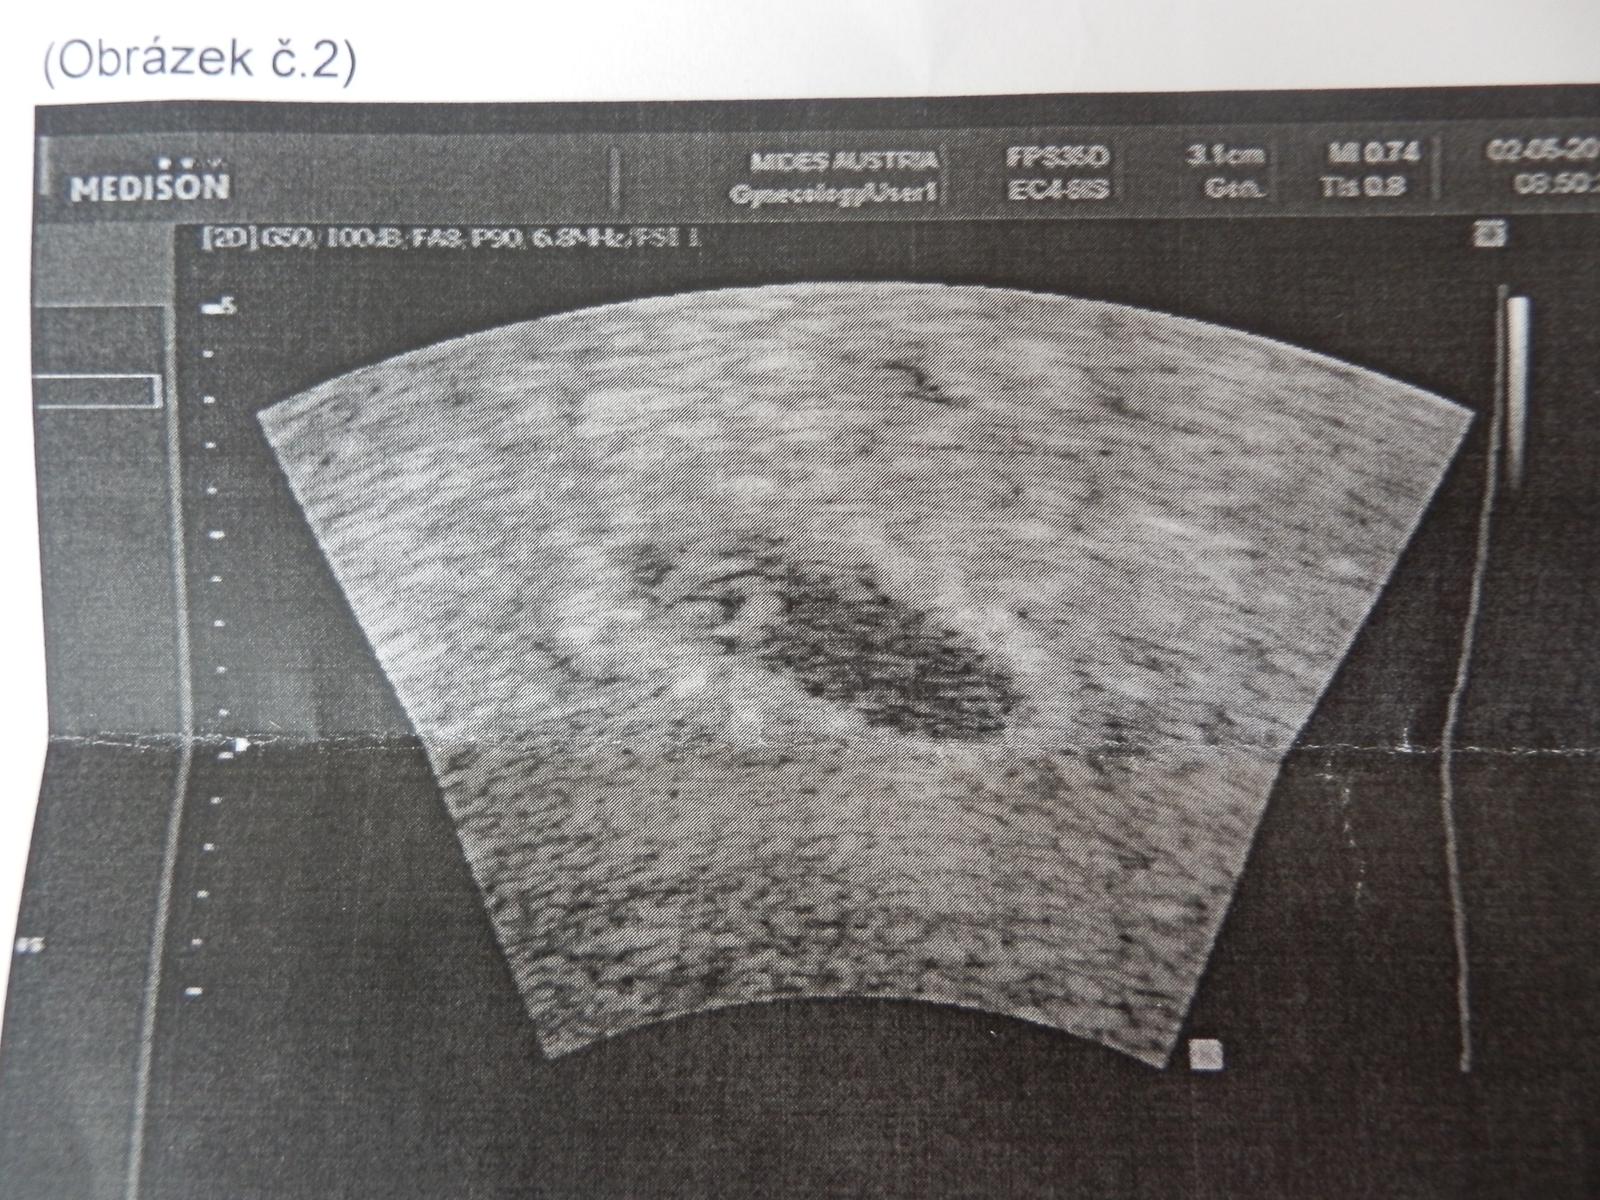

Holky, tak je půl 11, @antana123 už viděla bublinku 🙂 Těším se, co napíše 🙂

@antana123 jééé Anetko!!! To je krááásné! Doma bude oslava! Moc gratuluju!! 🙂

@antana123 držím pěsti, ať máte všechno v pořádku a kráásně rostete i nadále 🙂 🤐

@matysikovad doufáme 😉 dostala sem utrogestan 2-0-2 a prednison 1/2tablety denně a brali mi krev na genetiku k vůli těm potratům předešlím tak jsem zvědavá na co příjdou